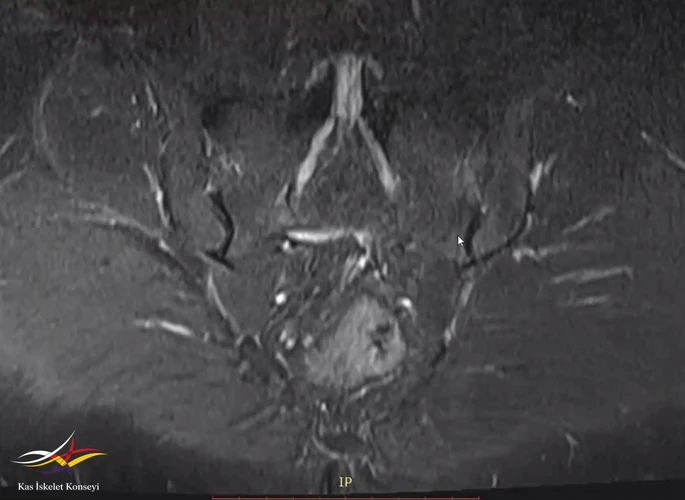

Resim 3. Sakroilak MRG